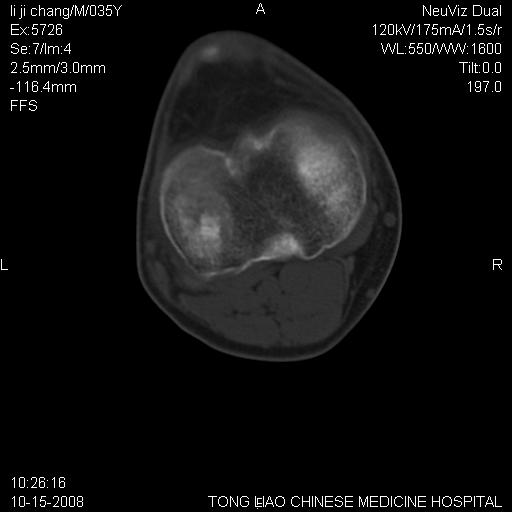

男,35岁,骨科诊断骨性关节炎。继往使用过激素,现股骨头坏死。膝关节病变,请会诊

一元论-----亦考虑为坏死

支持考虑无菌坏死

支持无菌坏死伴退行性骨关节病.

剥脱性骨软骨炎:是一种关节下软骨及软骨下骨缺血性坏死。

支持 无菌性坏死伴退行性骨关节病。